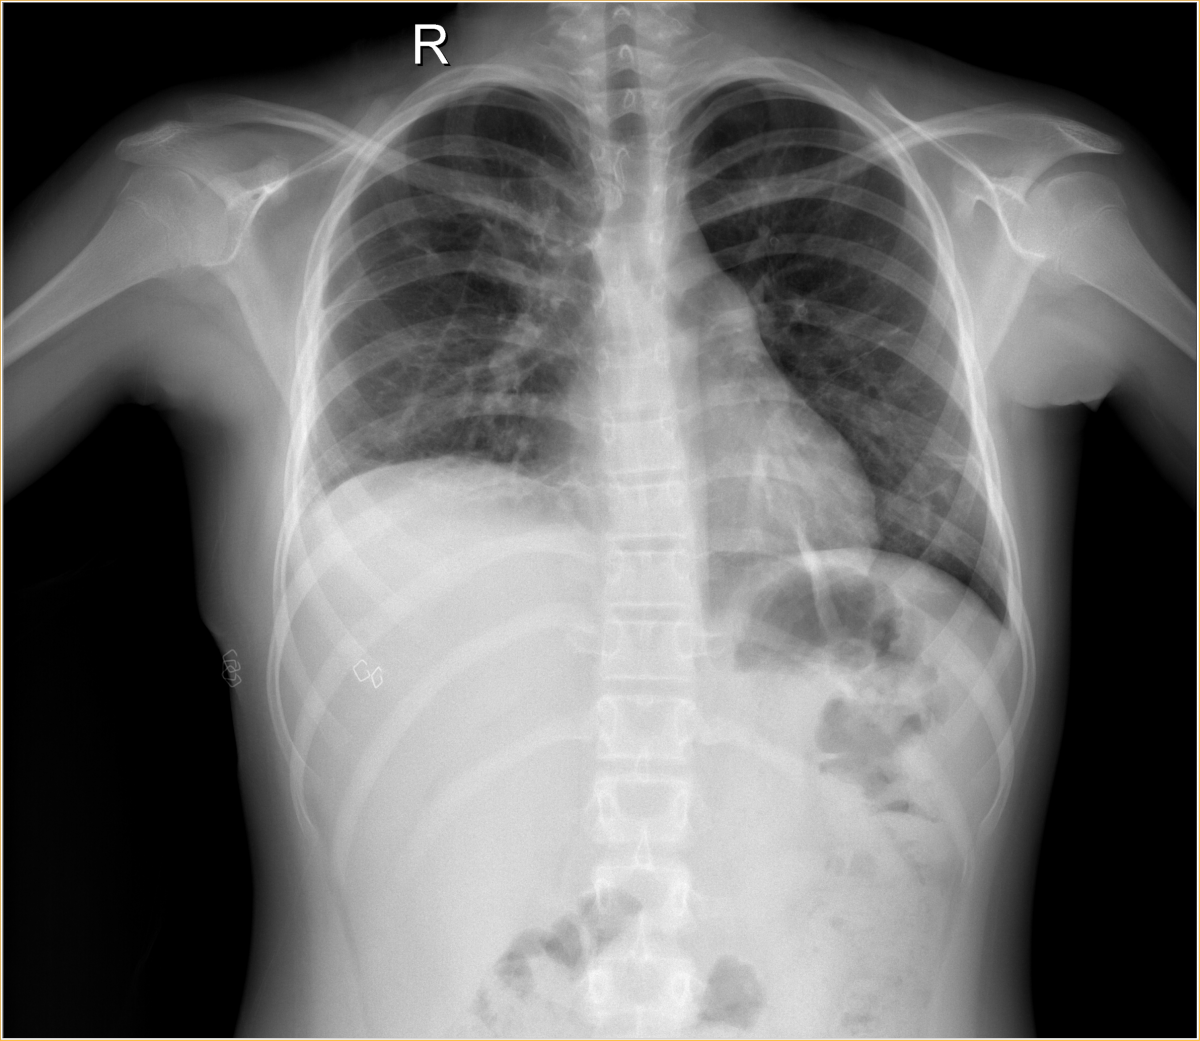

DIT decortication should be considered adequate when all pleural contents are drained, the fissures are opened, the lung is freed from the diaphragm, there is no symphysis of the diaphragm to the chest wall, and there is free expansion of the lung (Videos 8, 9). The previous chest drain site is debrided with excision of skin margin, and 28 Fr chest drains are placed anteriorly and posteriorly through the two incisions (Video 10). Postoperatively, suction is applied to the chest drains routinely, and they usually are removed on the 2nd and 3rd postoperative day when drainage is less than 200 ml in 24 hours (Figure 2).

Figure 2: Chest x-ray after tube removal.